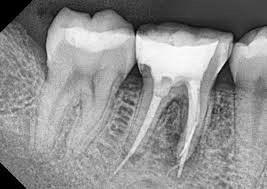

This category involves ledge formation, cervical, mid-root, or apical perforations, instrument separation, and canal blockage.

These can include iatrogenic perforations, ledge formation, canal blockage, instrument separation, and untreated anatomy, which can all impact treatment outcomes.